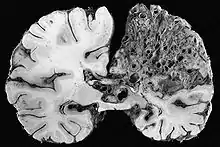

- angiome caverneux (ou « cavernome cérébral ») ; malformation vasculaire située en grande partie dans le cerveau, généralement non détectée, sauf lorsqu'elle cause des crises convulsives ou des hémorragies cérébrales (fréquence : 1 sujet sur 1 000, avec forme familiale dans 20 % des cas). Trois gènes situés sur les chromosomes 7 et 3 semblent impliqués ;